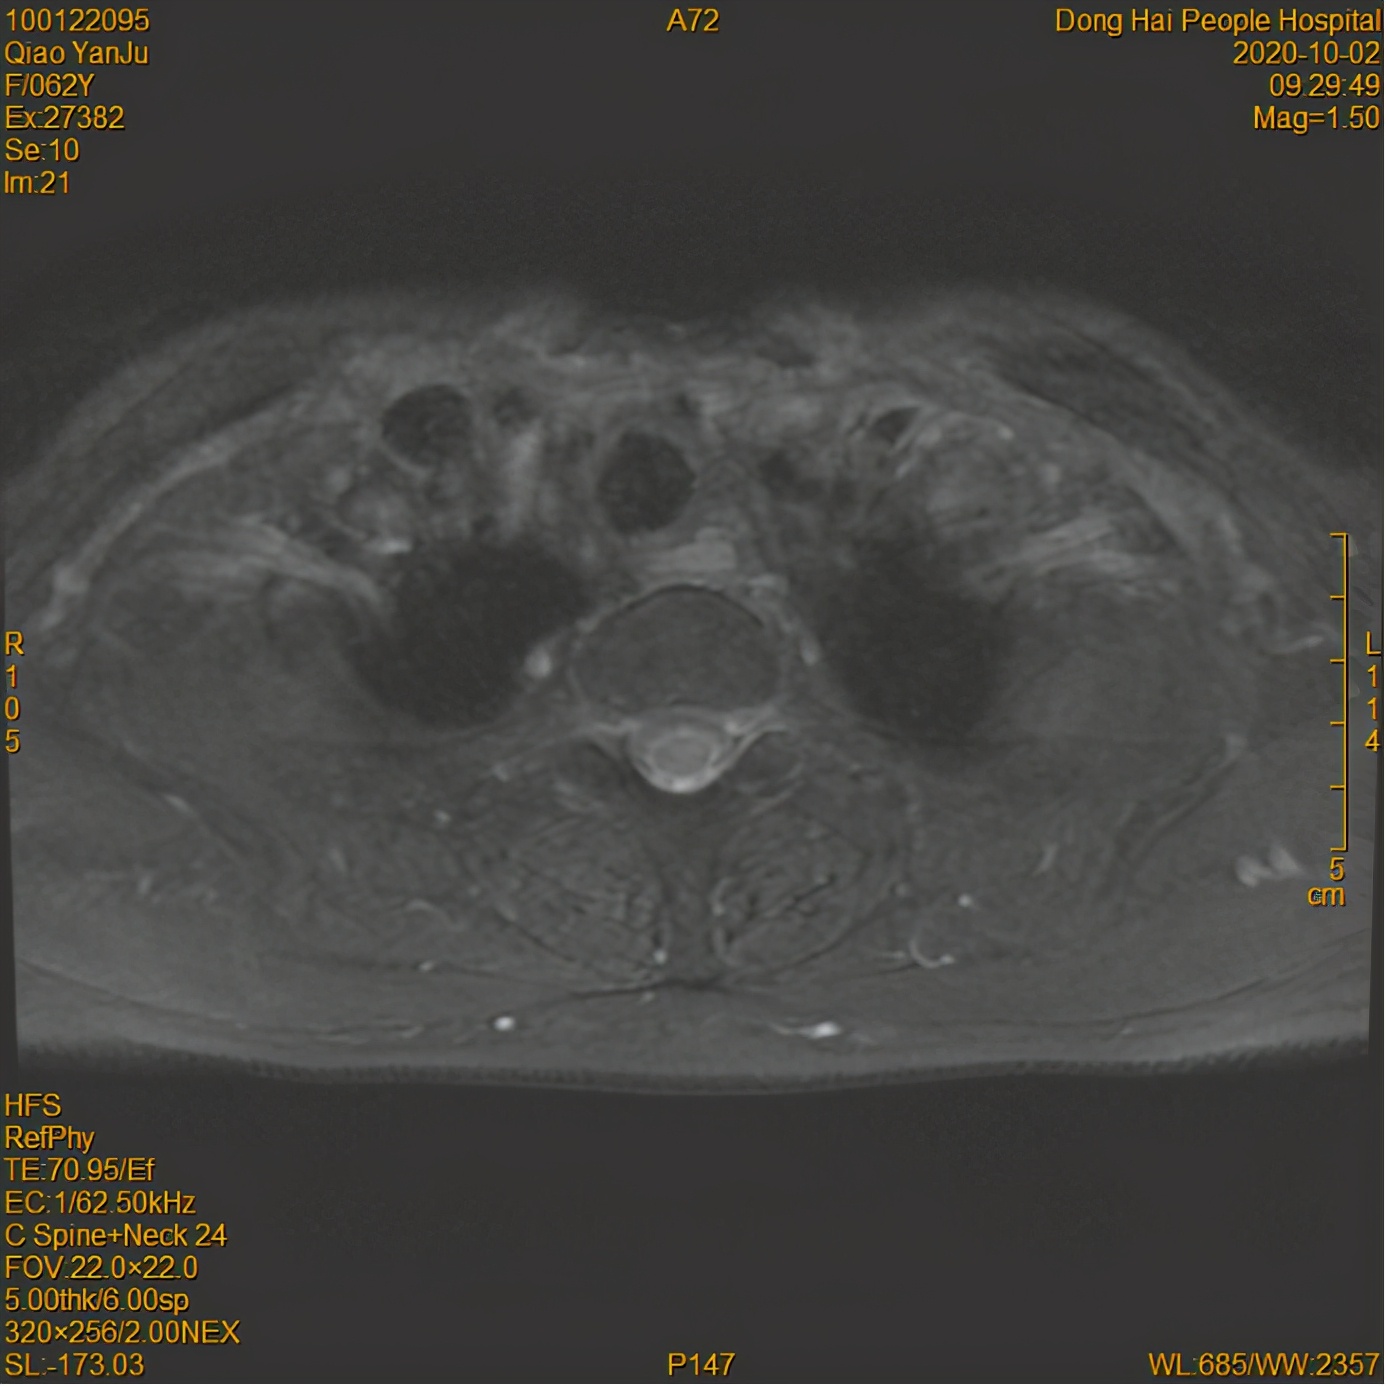

放疗后

经过8个月的放疗后,乔某鼻咽部肿瘤、颈部淋巴结退缩明显,多次复诊肿瘤控制较好。乔某的家人也松了一口气,发现放疗的效果确实好,而且人也不至于那么痛苦。